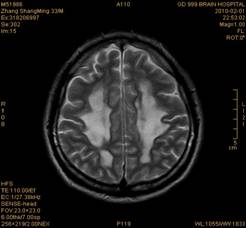

案例2 患者,女,30岁,二氯乙烷中毒性脑病的头颅MR。表现为双侧大脑半球皮层下白质、双侧外囊、双侧苍白球及双侧小脑齿状核内广泛片状、斑片状长T1长T2异常信号影,FLAIR序列呈高信号,增强后病变未见明显强化。

给予抗炎、脱水、疏通血管及营养神经等药物治疗。经过40天的对症治疗,痊愈出院。